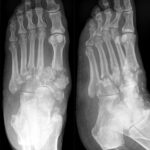

[doctormodu]1 accessory navicular bone x-ray

13 부주상골증후군 Accessory navicular bone, Prehallus

닥터모두

3 발목, 발4하지Lower Extremities

2025.10.24

41

#8